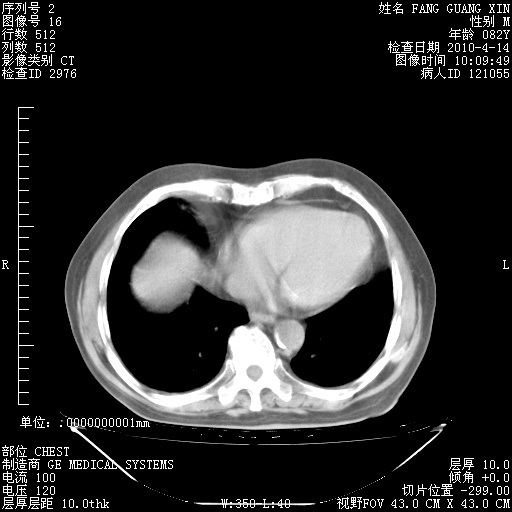

4月14日肺部CT

23.JPG

24.JPG

25.JPG

26.JPG